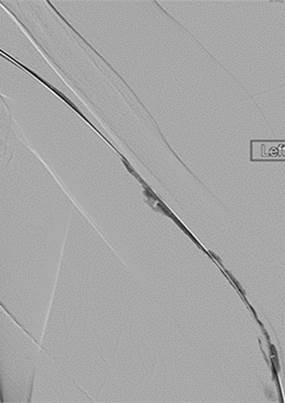

Initial central venogram confirming patency of central veins.

Underlying stenosis in cephalic arch responsible for thrombosis.